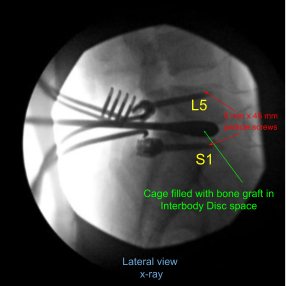

Once the dissection was done, the decision was made to put pedicle screws in both pedicles of S1 and L5. Drill was used to mark a pilot hole and a gearshift was used to guide the hole through the pedicle of S1 on either side under fluoroscopic guidance. Ball-tip sound was used to check the integrity of the canal.

Then 40 mm x 6 mm of pedicle screws (Depuy Synthes) were inserted on either pedicle of S1 and checked under fluoroscopy and found to be in satisfactory position. Similarly, a pilot hole was made with the use of drill on either side of the pedicle of L5 followed by a gearshift to find the path under fluoroscopy. A ball-tipped probe was again used and all the walls were found to be intact. Again, tapping was done and 6 mm x 45 mm pedicle screws were inserted in either pedicle.

A trial cage was inserted and checked under fluoroscopy and it was decided to put a 9 mm x 36 mm titanium cage. Allograft was used and mixed with morselized auto bone graft of the lamina and spinous process. The cage and disc interspace was filled with bone graft and the cage was inserted and checked under fluoroscopy, found to be in satisfactory position.